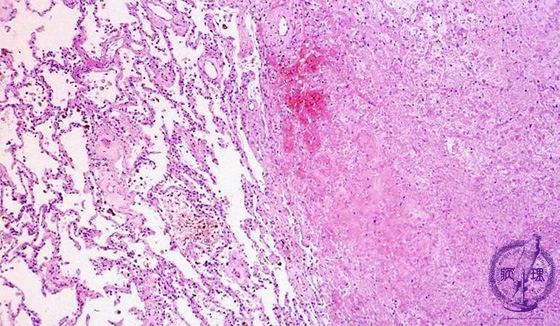

- (2)Hemorrhagic infarct of lung

Microscopic view (HE stain, low power view): On the right is an infarcted area associated with alveolar hemorrhage (arrow). Despite parenchymal cell necrosis, the outline of alveoli and nuclei remain faintly visible but nuclear staining is reduced (coagulative necrosis).